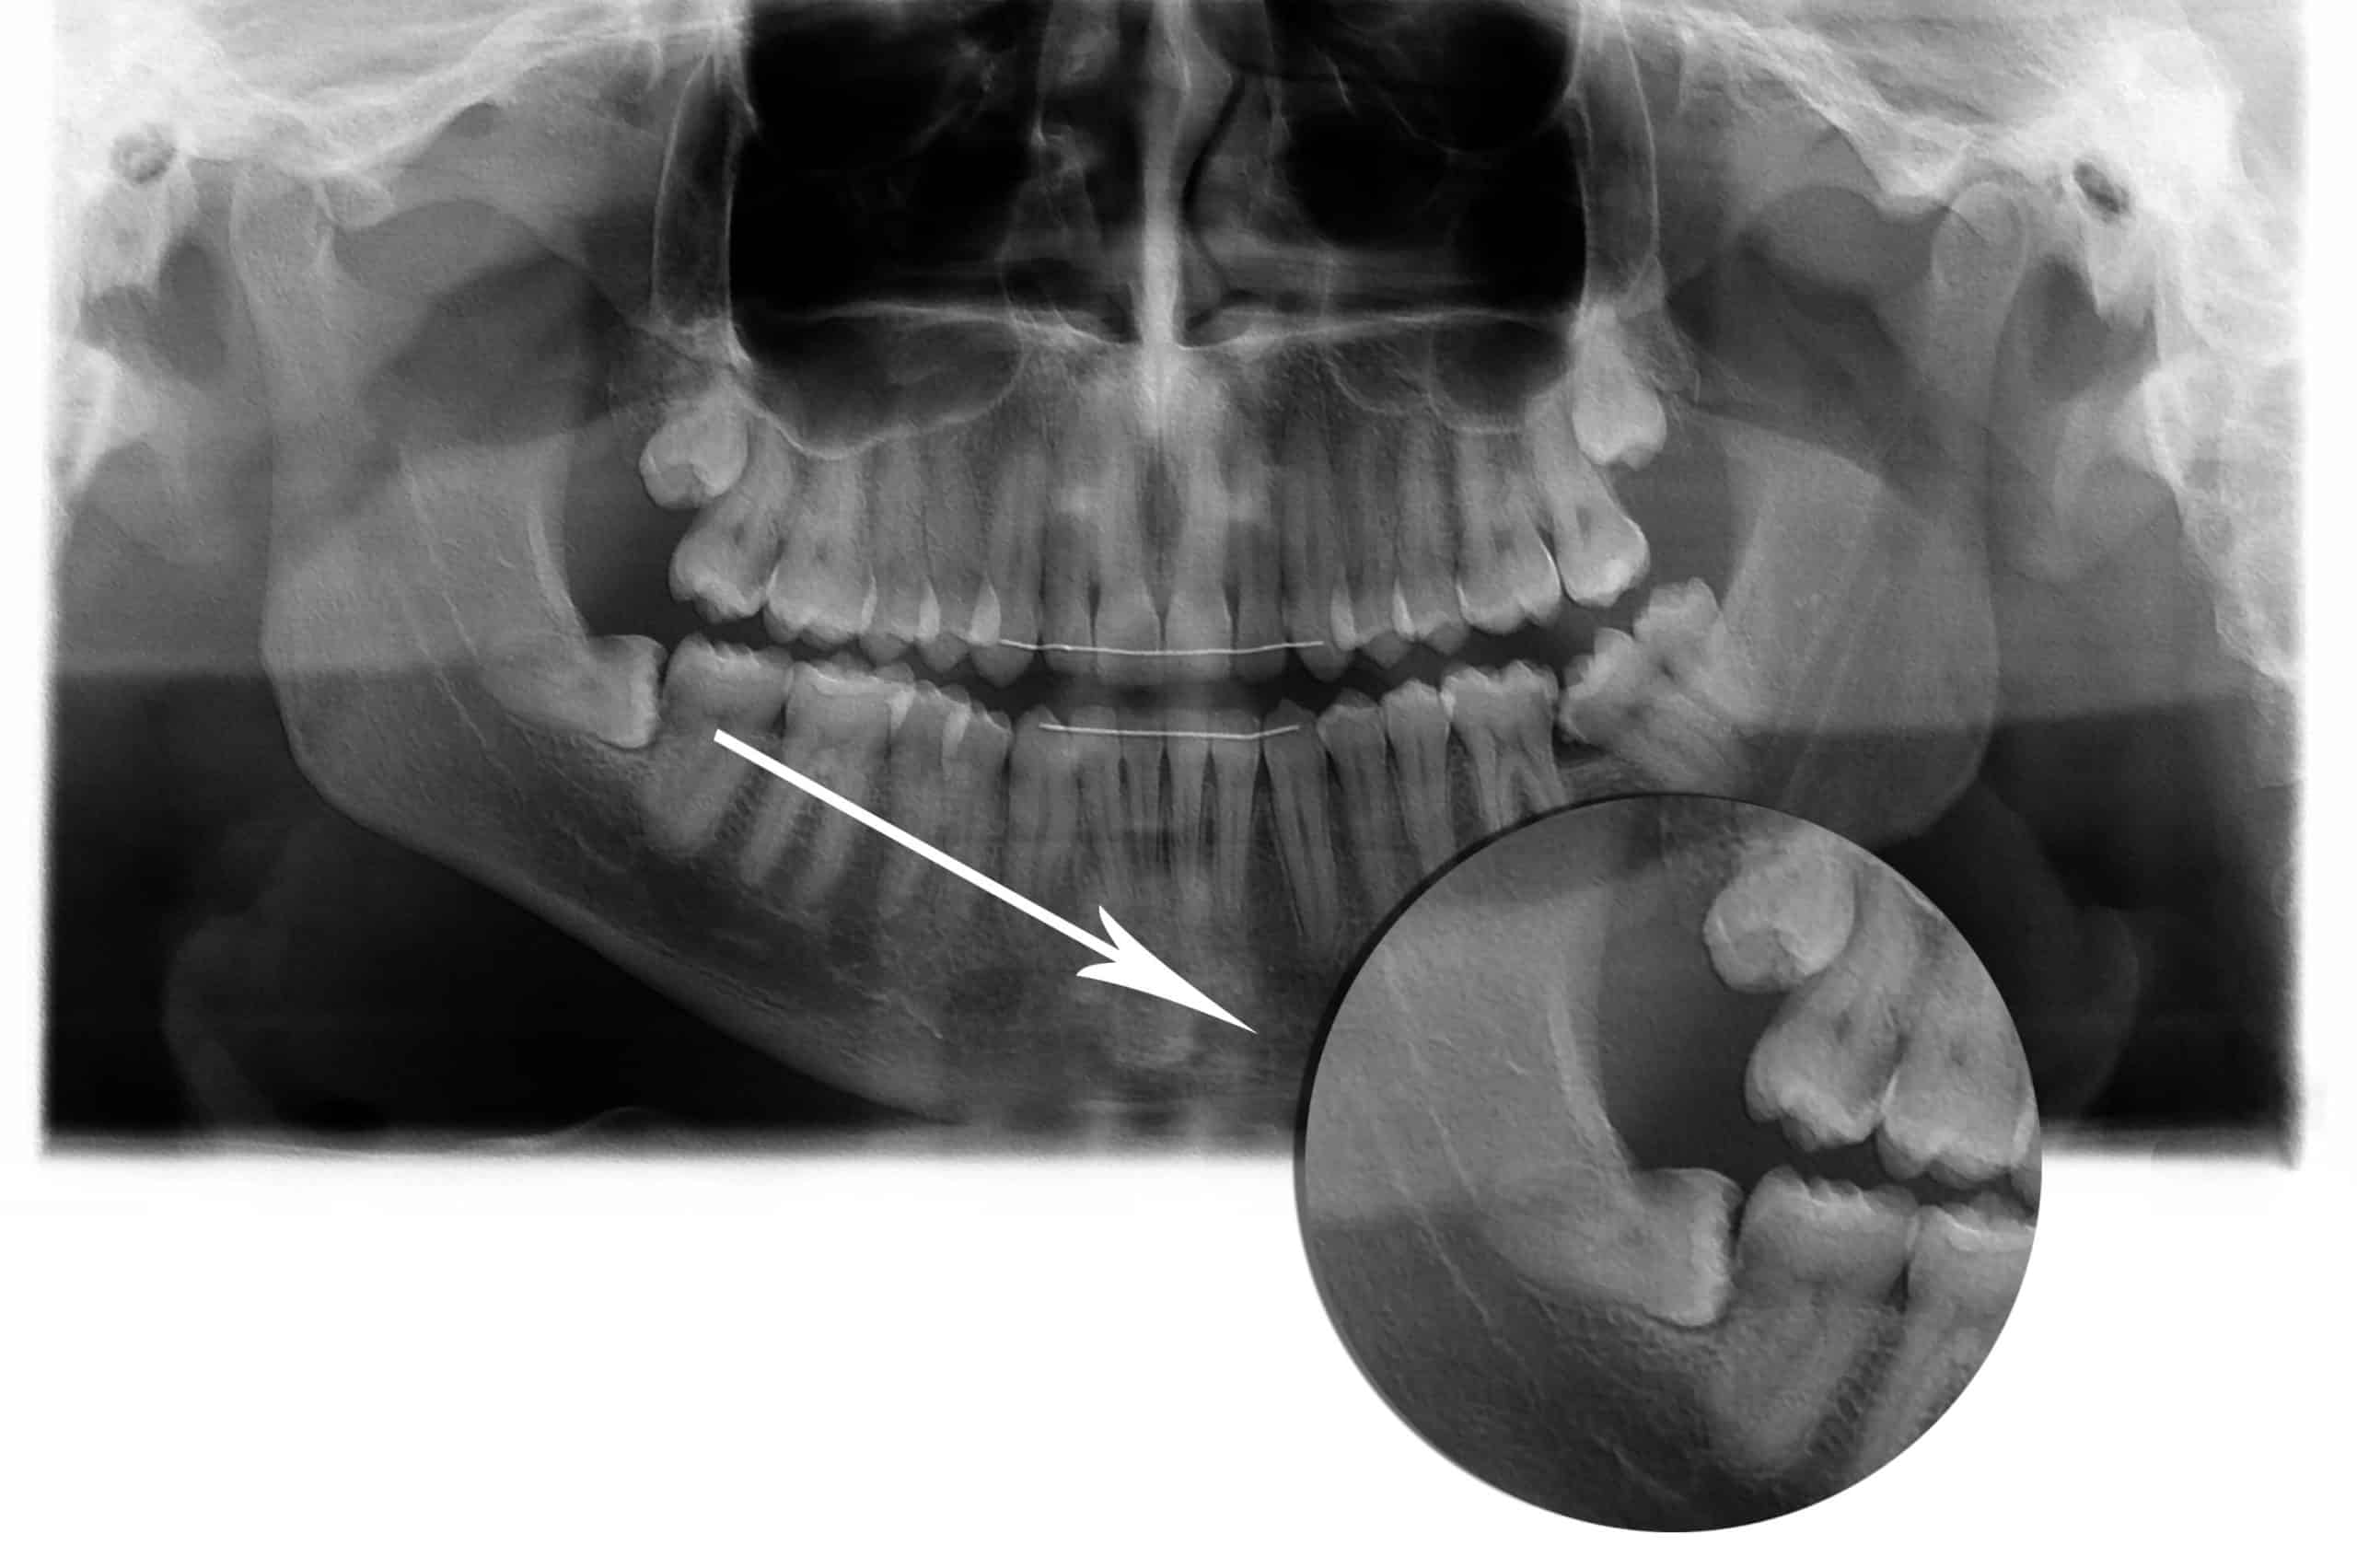

במצבים מסוימים יש צורך בעקירת שיניים:

שן עם כותרת הרוסה, שן ניידת מאוד כתוצאה ממחלת חניכיים מתקדמת או חבלה, שן שבורה שאינה ניתנת לשיקום, שיני בינה שאין להן מקום בלסת ועוד.

לאחר בדיקה קלינית וצילום רנטגן של השן, מבוצעת העקירה בהרדמה מקומית.

כאשר אין אפשרות לעקור את השן ללא חיתוך החניכיים, לדוגמא במקרה של שן בינה כלואה, יש צורך בביצוע של עקירה כירורגית.

לאחר עקירת שן בינה כלואה בעקירה הכירורגית, תופרים את החניכיים.